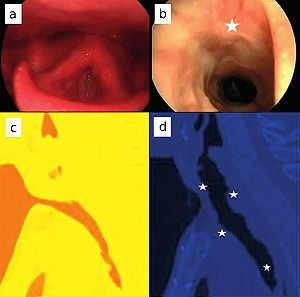

Publication: World Neurosurg. 2015 Dec 27. PMID: 26732948

Institution: Department of Neurosurgery, People's Liberation Army General Hospital, Beijing, China. Background/Purpose: OBJECTIVE: To investigate the feasibility and reliability of virtual endoscopy (VE) as a rapid, low-cost and interactive tool for suprasellar arachnoid cysts (SACs) diagnosis and surgical planning. Methods: 18 SACs patients treated with endoscopic ventriculocystostomy were recruited, and same number of endoscopic third ventriculostomy treated patients was randomly selected as VE reconstruction control group. After loading their DICOM data into free software 3D Slicer, VE reconstruction was independently performed by 3 blinded clinicians and the time required for each reconstruction was recorded. Other 3 blinded senior neurosurgeons interactively graded the visibility of VE by watching video recordings of endoscopic procedures. Based on the visibility scores, Receiver Operating Characteristic (ROC) curve analysis was used to investigate the reliability of VE to diagnose SACs, and the Bland-Altman plot was employed to assess the VE's reliability for surgical planning. In addition, intra-class correlation coefficient (ICC) was calculated to estimate the consistency among the results of 3 reconstructing performers. Results: All 3 independent reconstructing performers successfully completed VE simulation for all cases, and the average reconstructing time was 10.2±9.7 minutes. The area under ROC curve of cyst's visibility score was 0.96, implying its diagnostic value of SACs. Bland-Altman plot indicated good agreement between VE and intraoperative viewings, suggesting the VE's anatomical accuracy for surgical planning. In addition, ICC was 0.81, which revealed excellent inter-performer consistency of our simulation method. Conclusion: This study substantiated the feasibility and reliability of VE as a rapid, low-cost and interactive modality for SACs diagnosis and surgical planning. |